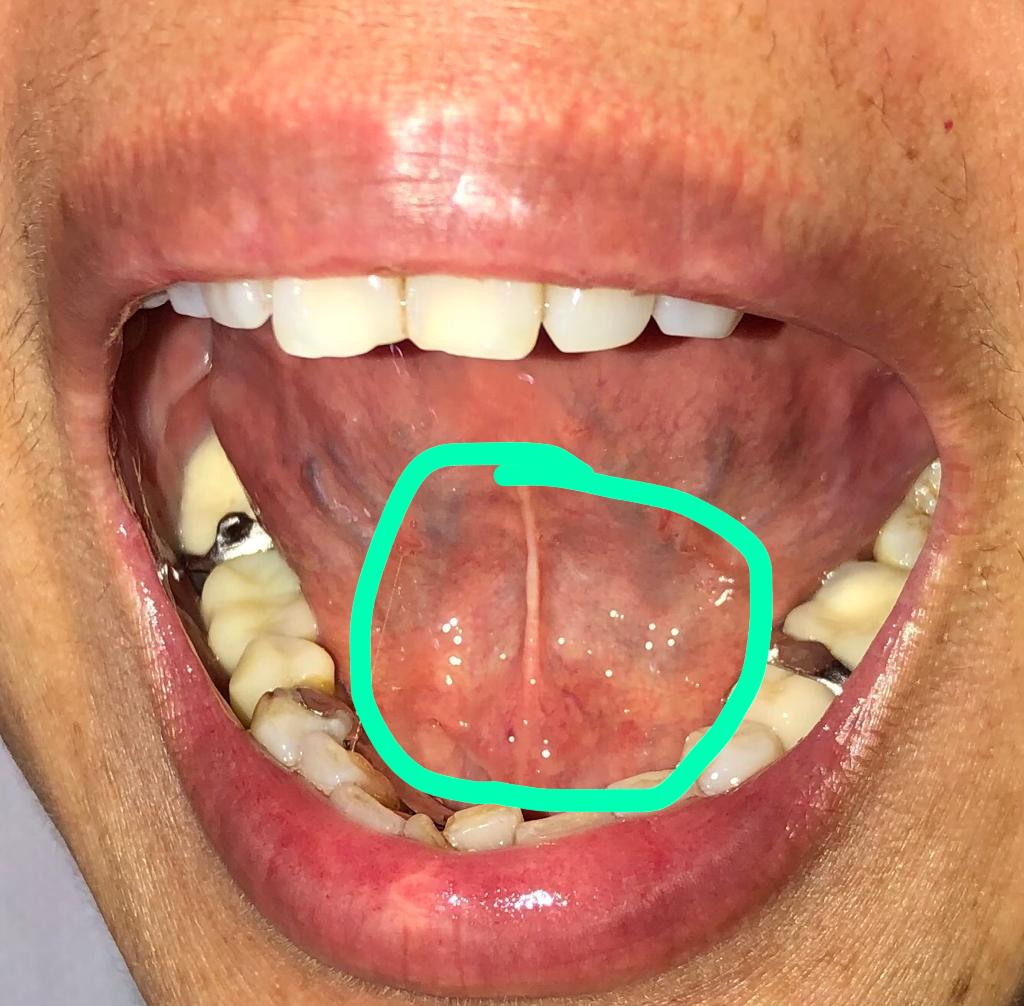

須要舌及舌底的照片, 先張開口, 跟住自然把舌伸出, 不要用力. 舌底要照下面的筋肉. 不清楚可看以下樣本: 謝謝合作!

- 第一張, 從容的張開嘴,放鬆把舌頭伸出. 頭微向上,令燈光可照到舌根處。注意我們想看到舌的根部 (即綠色圓圈部份)

- 第二張,把是舌尖頂上顎,頭微向上,令燈光可照到舌根處。注意我們想看到舌的根部 (即綠色圓圈部份)